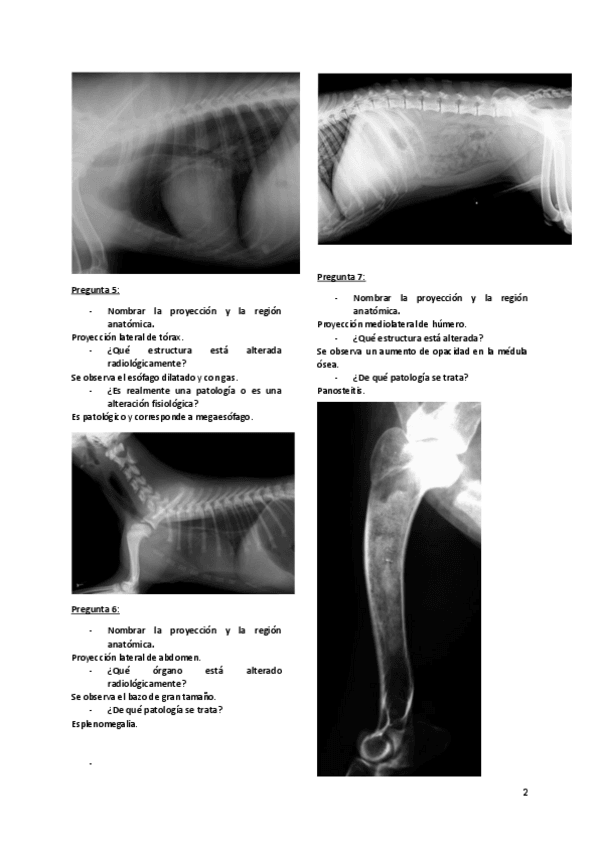

Imágenes de radiografias explicadas

He publicado nuevos apuntes de 3º Diagnóstico Por la Imagen: Imágenes de radiografias explicadas

Rx-equina-1.pdf

Rx-abdomen.pdf

Rx-torax.pdf

Rx-cuello-y-torax.pdf

Rx-miembro-pelviano.pdf

Rx-miembro-anterior.pdf

apuntes